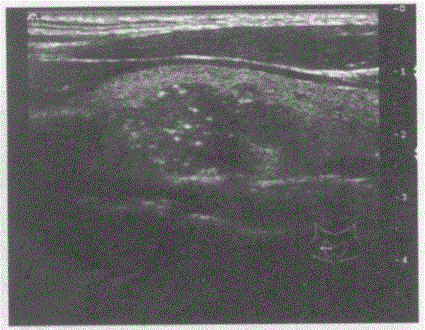

问题 临床资料:女,44岁,自述颈部不适,声音嘶哑两周余。 临床物理检查:甲状腺右叶扪及一肿物,活动度差。 超声综合描述:甲状腺形态、大小正常,右叶可见4.0cm×3.1cm低回声区,边界欠清,内回声不均,可见较多砂粒样强回声光点。 超声提示:

选项 A.甲状腺腺瘤(右叶) B.甲状腺癌(右叶) C.结节性甲状腺肿 D.毒性甲状腺肿(原发性甲状腺功能亢进)

答案 B